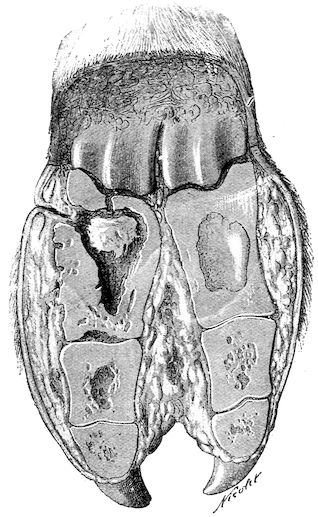

Fig. 8.—Transverse section through the middle region of the face in a pig suffering from osseous cachexia.

18In the final stages, the bones may be cut with a knife, and a time arrives when bony tissue seems completely to have disappeared; thus, as shown in Fig. 8 herewith, it was possible to cut the entire head of a pig into thin slices without the slightest difficulty. All parts of the head had been affected by the softening change.

From the chemical point of view, the diminution in mineral salts and in phosphate of calcium has long been recognised, but the degree of this change varies according to the phase. In human beings the proportions have been estimated as follows: Normal bone, 50 to 80 per cent. of phosphate of calcium; bone in persons suffering from osteomalacia, 5 to 20 per cent. of phosphate of calcium. The changes in the ossein have not been carefully studied. We only know that histologically the ossein becomes fibrillar, and that chemically it no longer retains its normal composition.